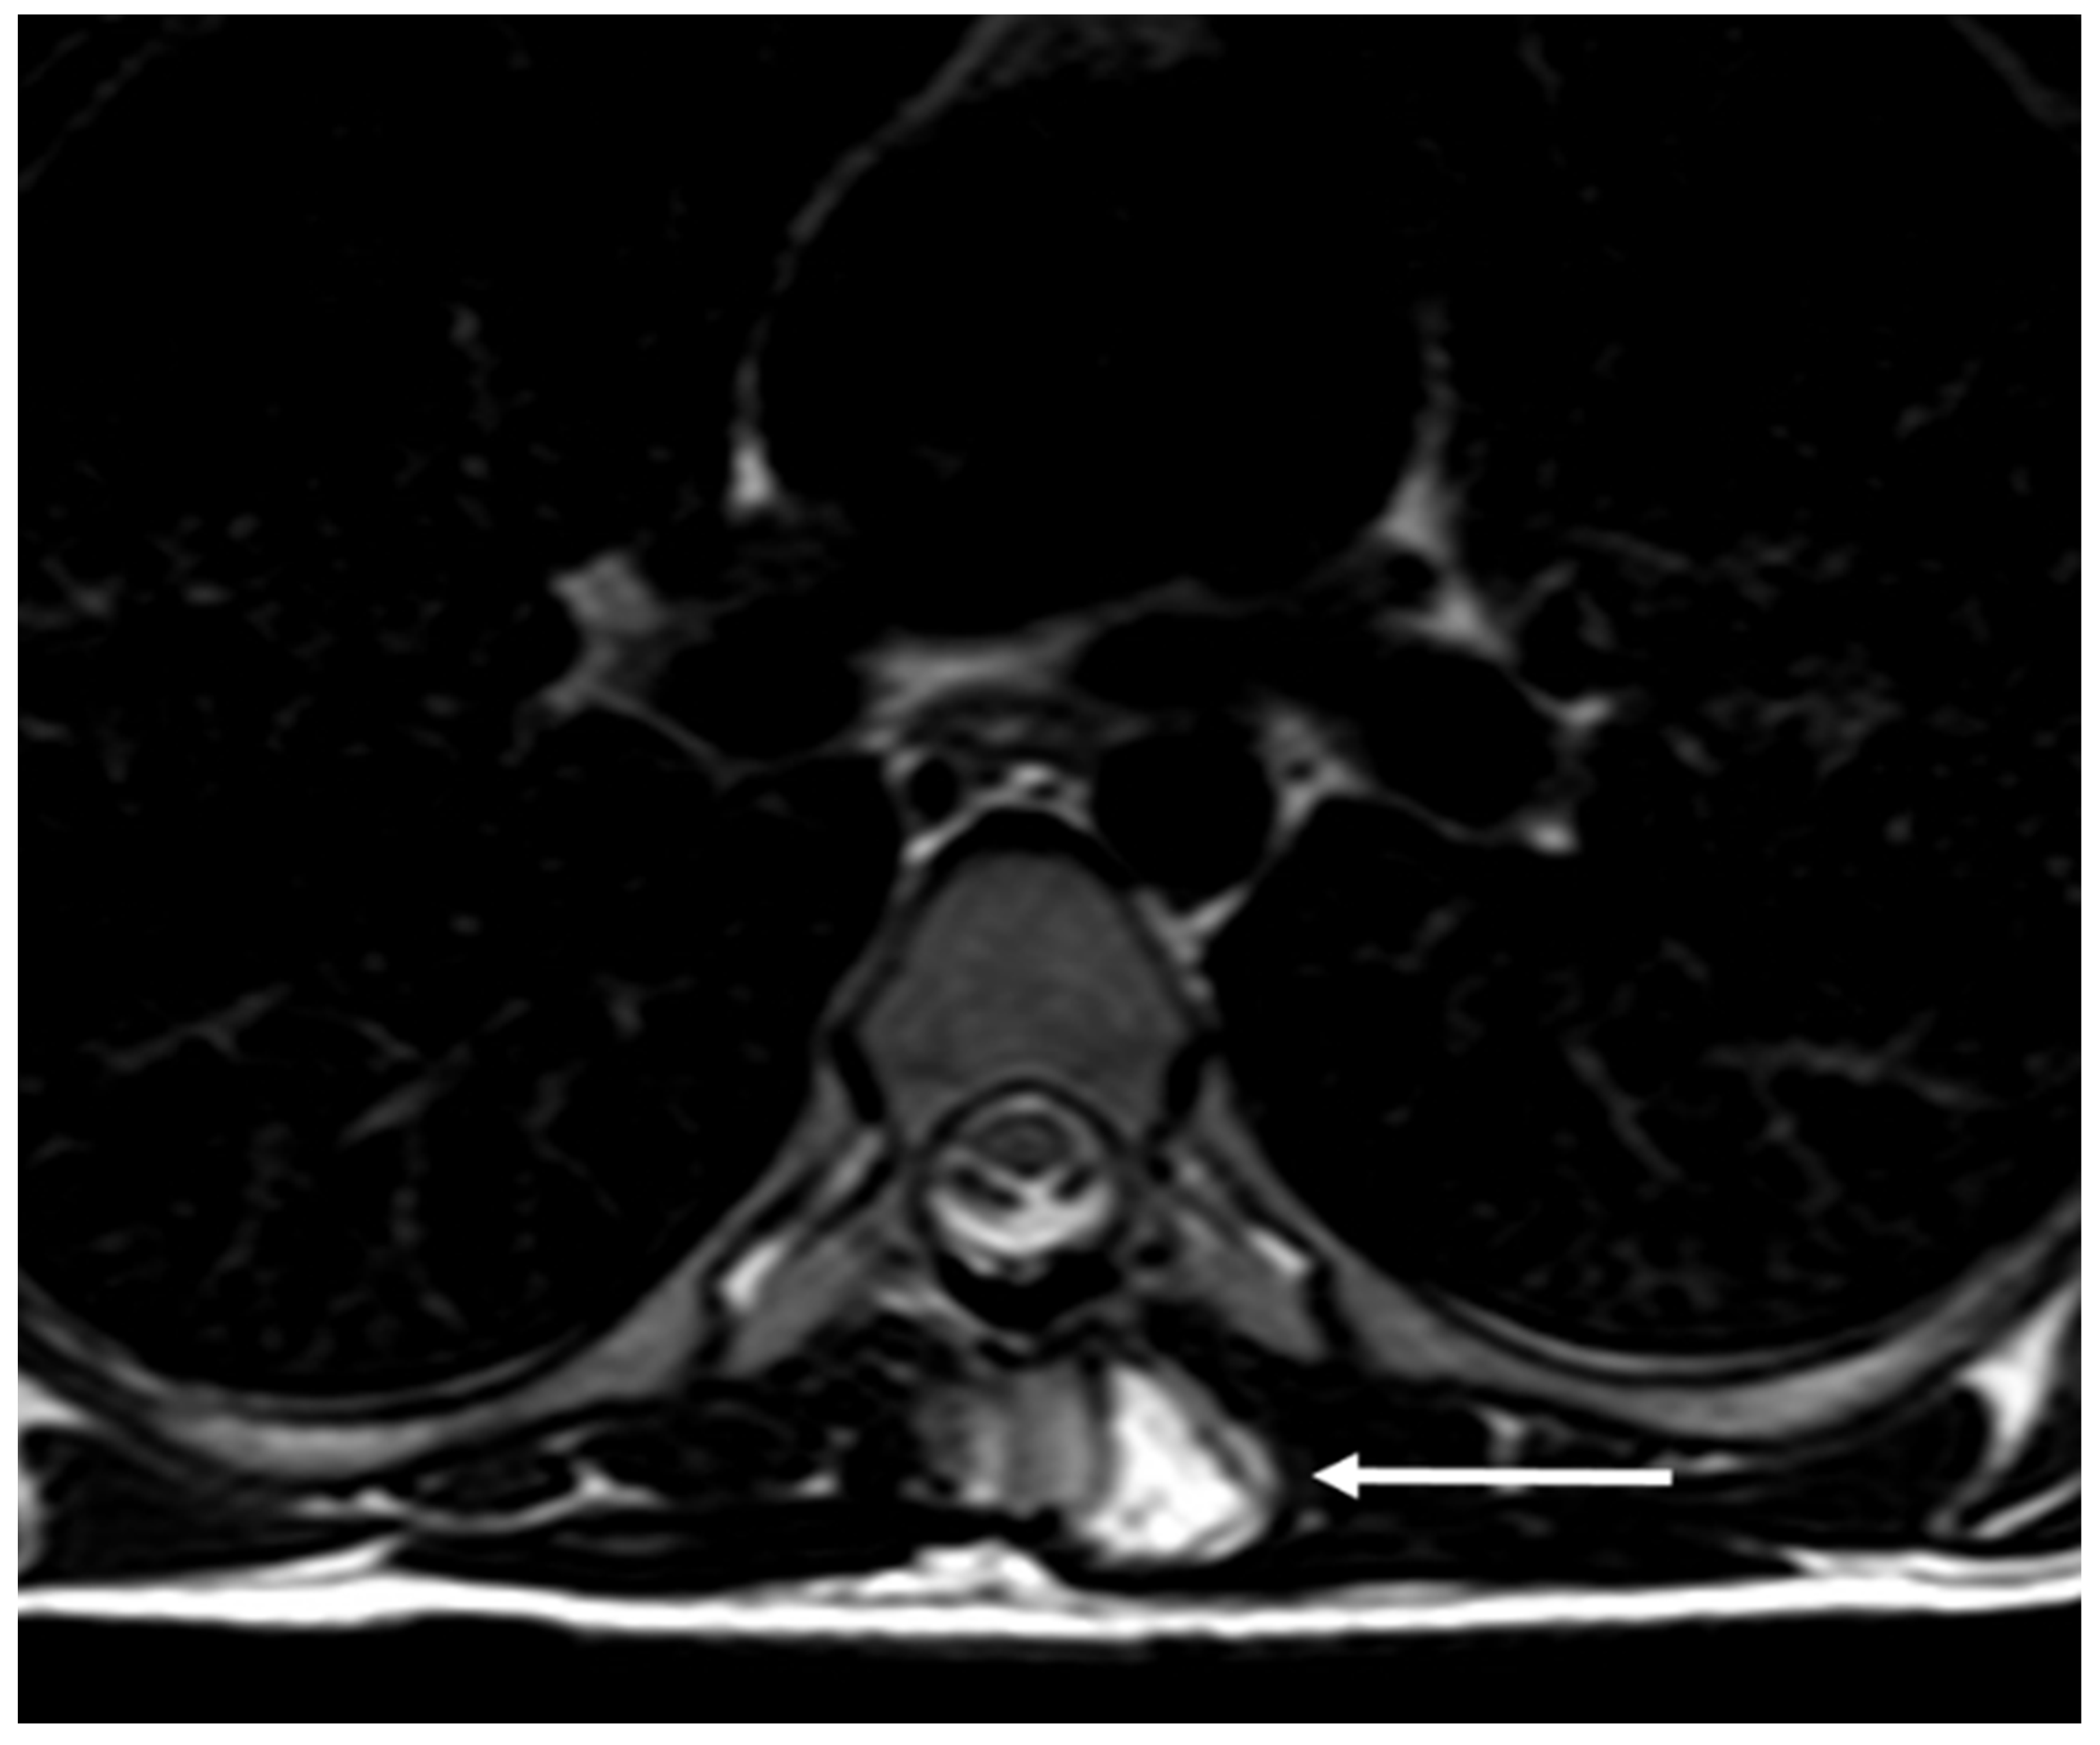

| Haemangioma | Honey comb appearance. ‘Corduroy’ and ‘polka dot’ signs. | Usually T1 and T2 hyperintense due to fat content. Signal drop out >20% on out of phase chemical shift imaging. |

| Simple bone cyst | Well defined lucent rim with narrow zone of transition. | Fluid signal lesion. May have some internal haemorrhage (high T1 signal). |